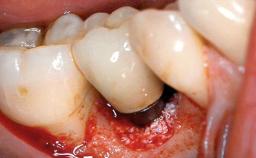

Management of a Fractured Implant Supporting a Screw-retained Metal-ceramic Restoration

The fracture of an implant after it has been restored is one of the most severe complications. It most frequently occurs in partially edentulous jaws (1.5%). Most implant fractures involve implants with a diameter of 3.75 mm made of commercially pure titanium (Eckert 2010). Unfortunately, many cases are not reported or documented by the clinicians involved in resolving the problems created by the fracture. This case report describes the management of an implant fracture at site 36 in a middle-aged male patient. The implant had been restored with a screw-retained metal-ceramic crown.